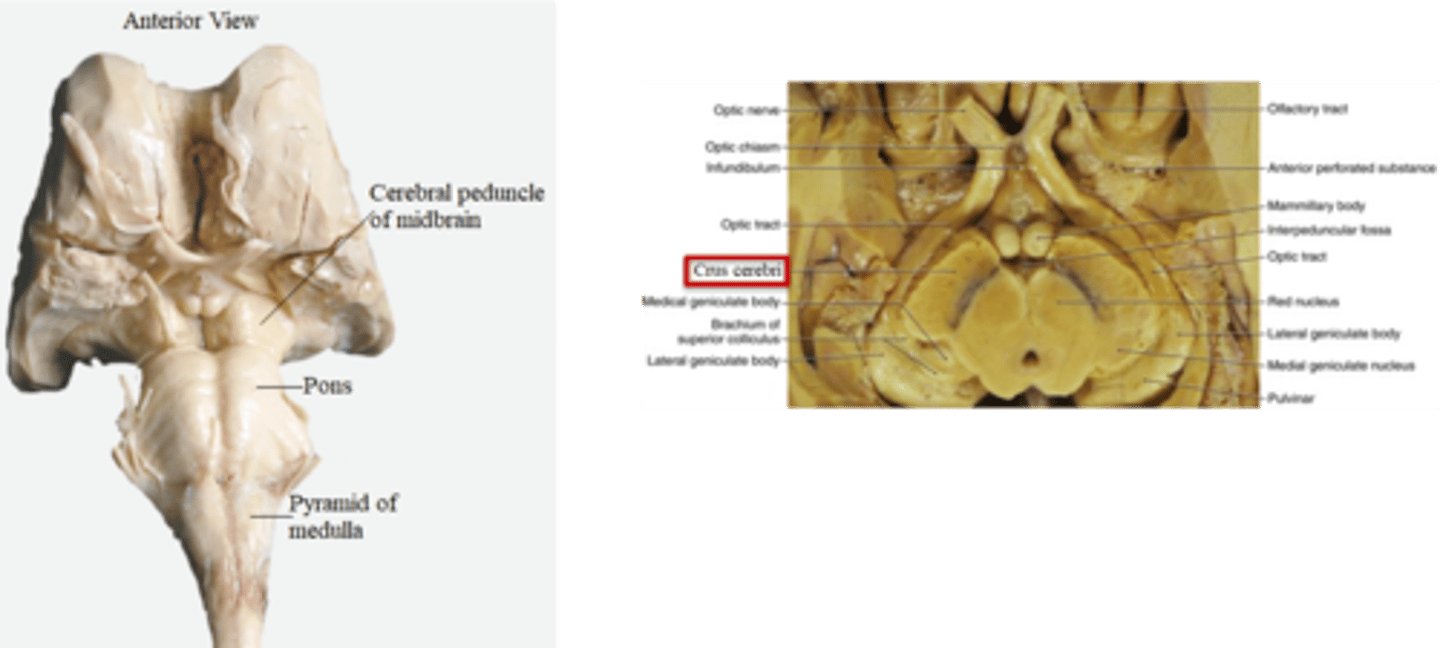

what are the 4 areas that the brainstem can be divided into (from posterior to anterior)?

1. tectum

2. ventricular system

3. tegmentum

4. basal portion

which area of the brainstem is the roof over the ventricular system?

tectum

which area of the brainstem makes up the core of the brainstem?

tegmentum

which area of the brainstem is situated most anteriorly?

basal portion

which region of the brainstem contains the cerebral aqueduct?

midbrain

looks like a hole in the center of the midbrain

cerebral aqueduct connects the 3rd and 4th ventricles

what are the 2 components that make up the ventral and dorsal area of the pons?

1. basilar pons (ventral)

2. tegmentum (dorsal)

what component of the pons forms the floor of the fourth ventricle?

tegmentum